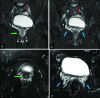

Disorder of sex development is an inclusive term that refers to any problem where the genital organ is atypical in relation to chromosomes or gonads. Ovotesticular disorder of sex development, which is formerly known as "true hermaphroditism," is the most rare form among all disorders of sex development in humans. It is characterized by the simultaneous presence of both ovarian and testicular tissues in the same individual and characteristically presents with ambiguous genitalia in neonates or infants. Herein, we present an unusual case of a 19-year-old individual with phenotypically nearly normal male genitalia who presented with the complaint of bilateral breast enlargement.